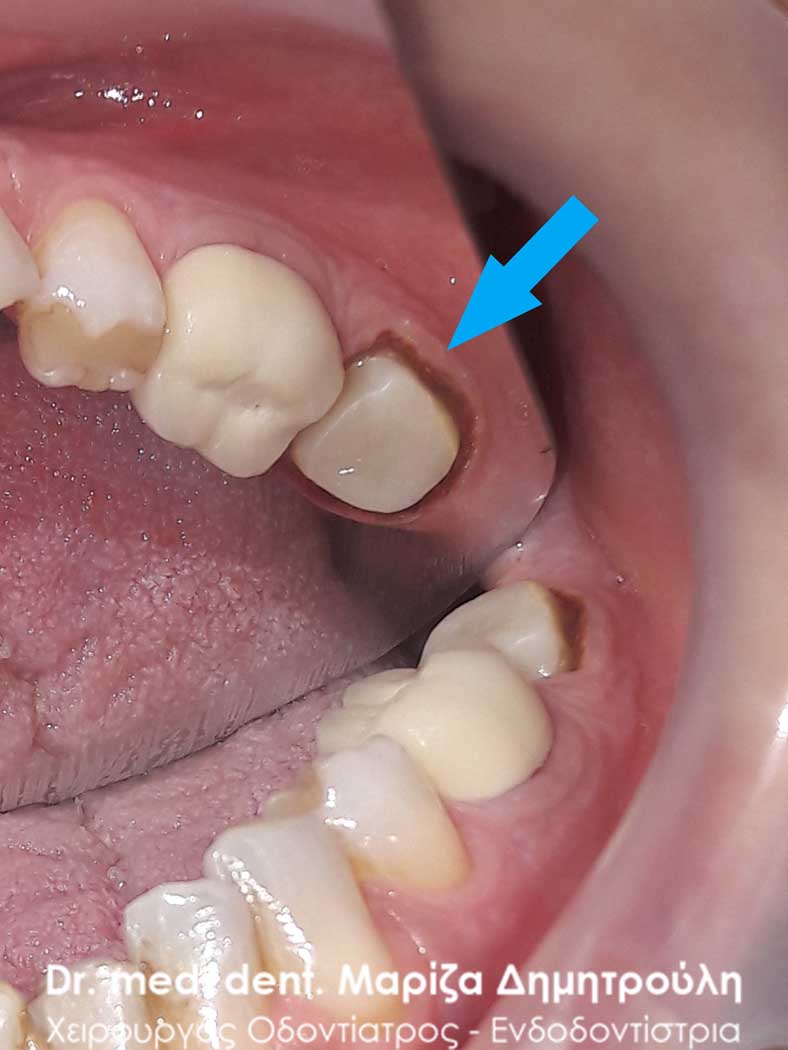

Αρχική εικόνα του παλιού μεγάλου σφραγίσματος

Κλινική εικόνα του μεγάλου οδοντικού ελλείμματος μετά την αφαίρεση του παλιού σφραγίσματος